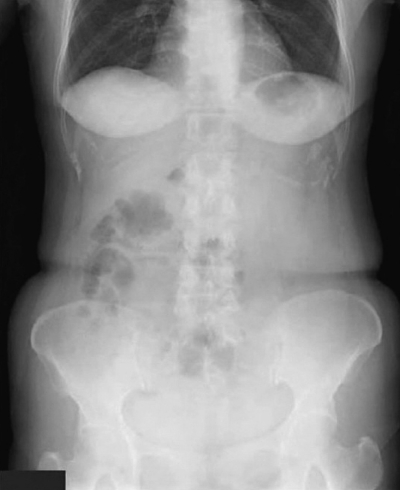

血液所見:赤血球 350万、Hb 11.0 g/dL、Ht 43 %、白血球 9,200、血小板 38 万。血液生化学所見:尿素窒素 19 mg/dL、クレアチニン 1.2 mg/dL。CRP 5.0 mg/dL。立位と臥位の腹部エックス線写真を別に示す。

立位